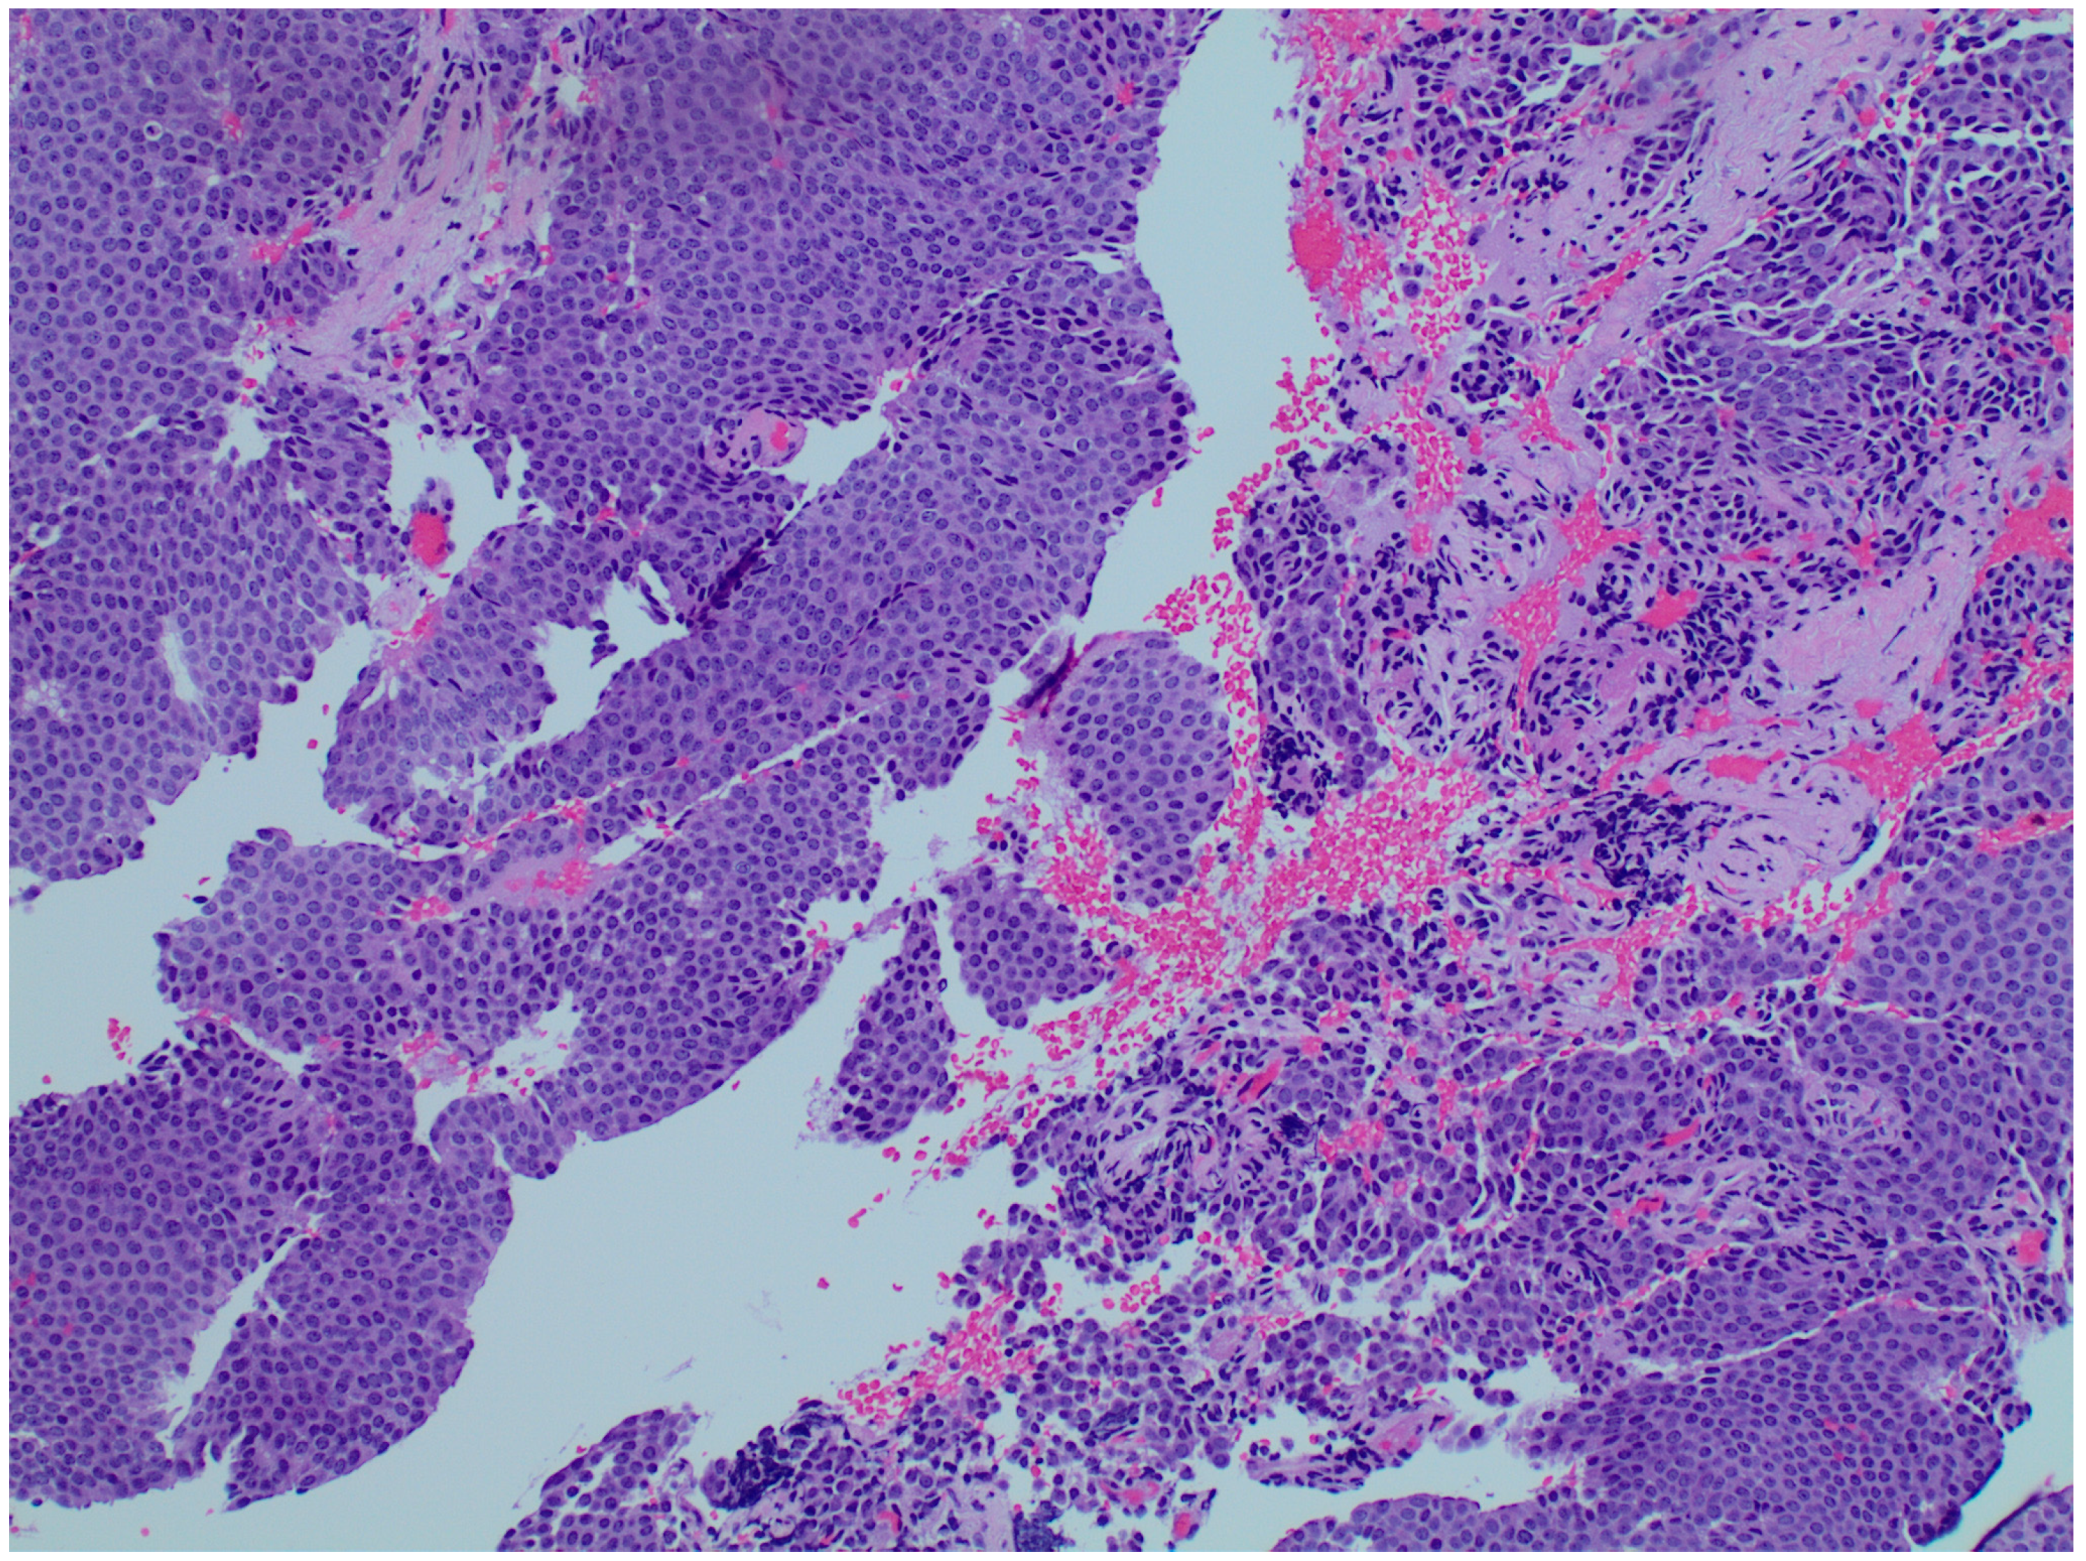

2. Case Presentation